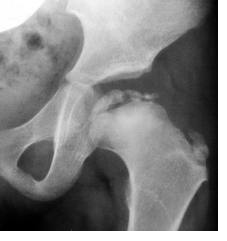

骨盤のくぼみに収まっている大腿骨頭に何らかの原因で血液の供給が十分に行き届かなくなって、骨頭が変形したり壊死したりする関節の病気です。

まず触診して痛み具合を見ます。そしてX線検査を行い見極めます。